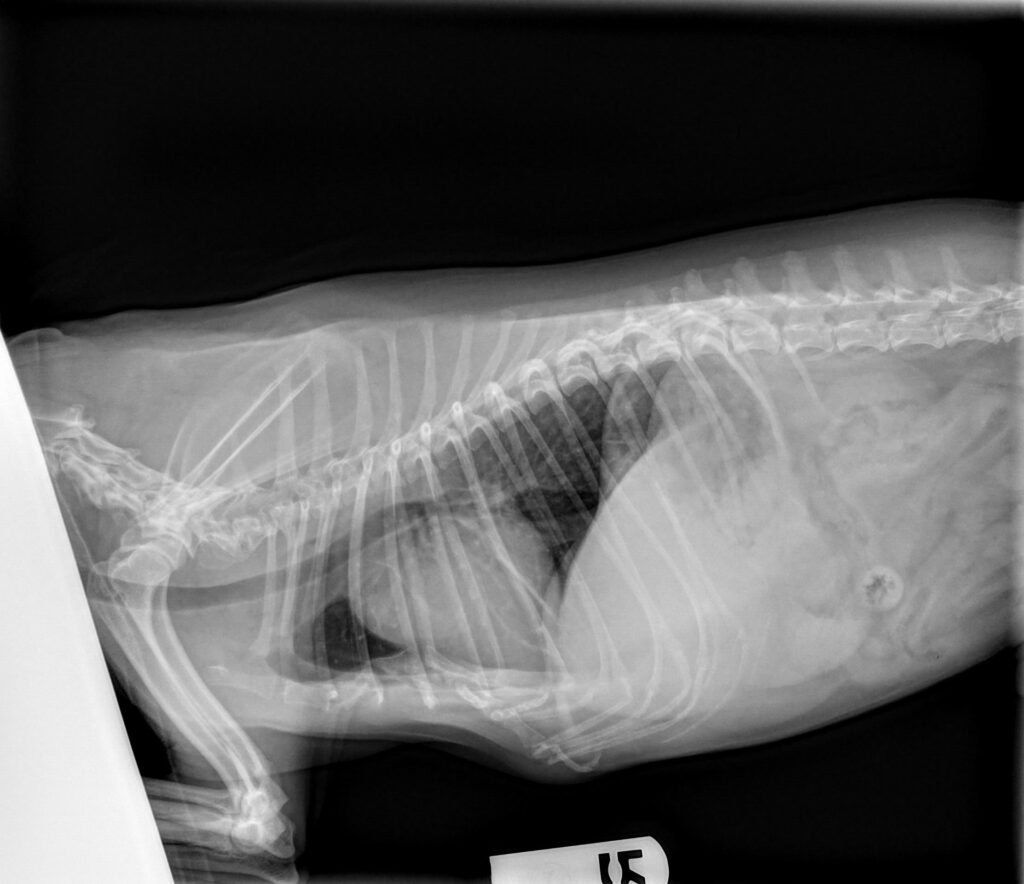

The patient presented for vomiting, labored breathing and a low appetite. The patient has a history of chronic valvular disease (previous echo read by Sonopath). He is currently managed on pimobendan, enalapril and furosemide. Radiographs showed cardiomegaly with possible mild pulmonary edema in the perihilar region.

Radiographs taken at the referring veterinary hospital: